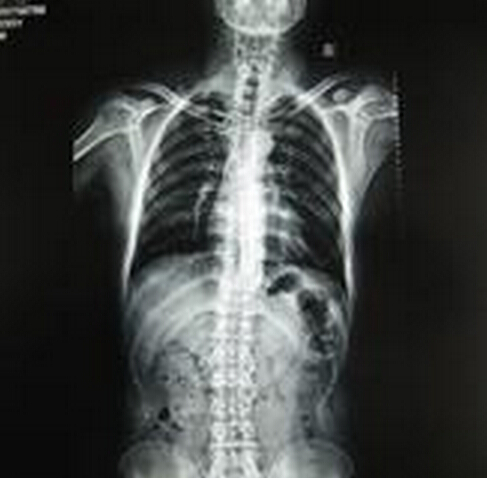

(图:李先生治疗前检查显示后背弯曲明显)

李先生经过第一次治疗后,疼痛就有缓解的迹象。经过连续两个疗程的治疗以后,李先生明显感觉到全身轻松很多,腰背部的僵硬疼痛感基本消失了。后经巩固治疗一个疗程后,检查各项指标均达到正常水平。

(图:在治疗后从李先生的检查报告可以看出后背弯曲度有所改善)